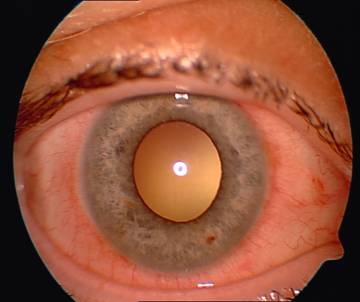

Examenul biomicroscopic al polului anterior deceleaza la OD congestie conjunctivala moderata mixta ,fine precipitate endoteliale corneene in jumatatea inferioara ,CA de profunzime medie cu Tyndall usor pozitiv, stroma iriana si guleras pigmentar de aspect normal, pupila centrala ,rotunda , reflexiva, cristalin transparent, tulburari in vitrosul anterior (fig.1) ; OS fara modificari patologice .

Fig. 1 Pol anterior -OD